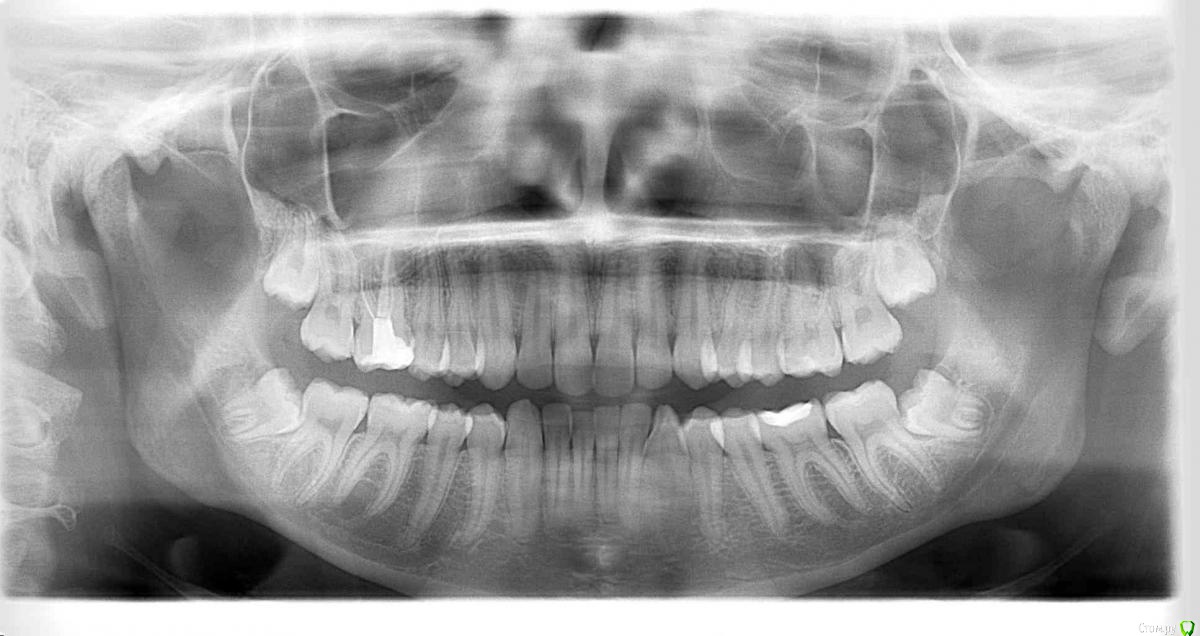

Orhan_dentist125 Опубликовано 11 марта, 2015 Поделиться Опубликовано 11 марта, 2015 ДД, коллеги. Видна ли на этом снимке киста 16 зуба?И что изображено над 26 и 27 зубом? Заранее спасибо Ссылка на комментарий

сирена Опубликовано 11 марта, 2015 Поделиться Опубликовано 11 марта, 2015 1.Не вижу2.Гайморова пазуха 1 Ссылка на комментарий

marialera Опубликовано 11 марта, 2015 Поделиться Опубликовано 11 марта, 2015 над 17 есть деструкция Ссылка на комментарий

red_butler Опубликовано 12 марта, 2015 Поделиться Опубликовано 12 марта, 2015 делайте прицельный снимок 1.7 2 Ссылка на комментарий

M@estro Опубликовано 13 марта, 2015 Поделиться Опубликовано 13 марта, 2015 а лучше - КТ 3 Ссылка на комментарий